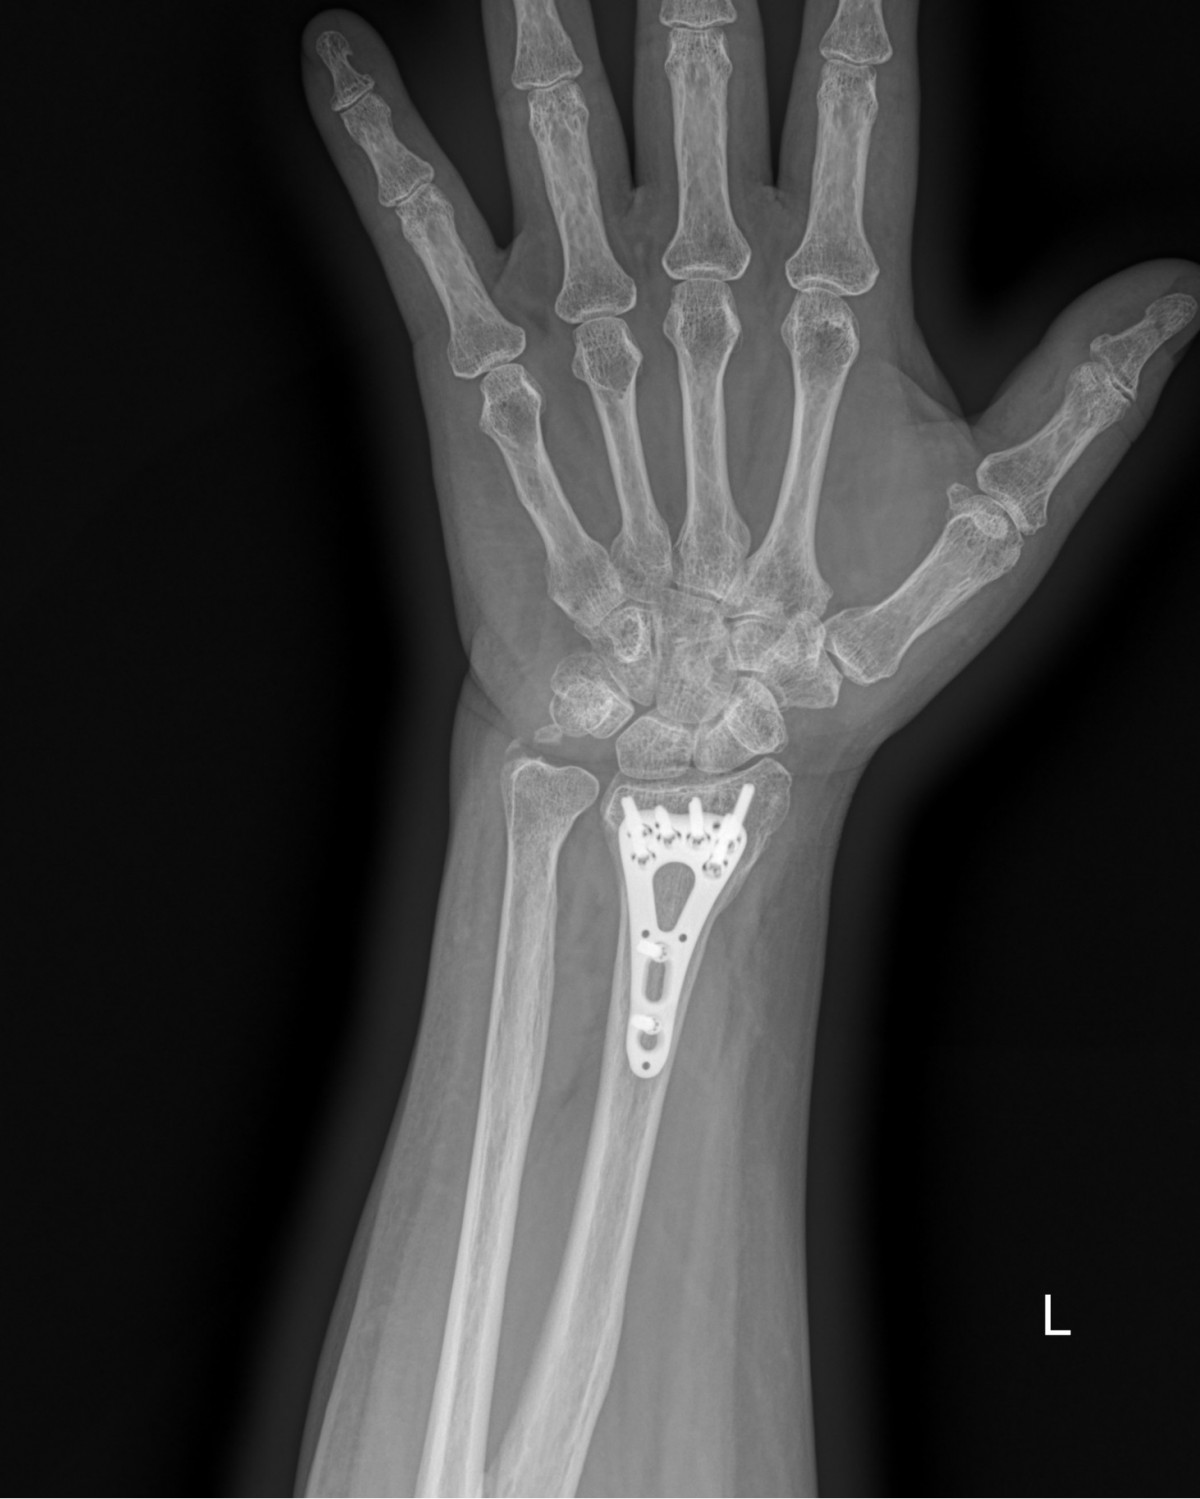

이재상원장님 손목 골절 수술 정명O 환자

dae765e4d9ac96aee867c9d6292d8784_1758002628_3506.jpg